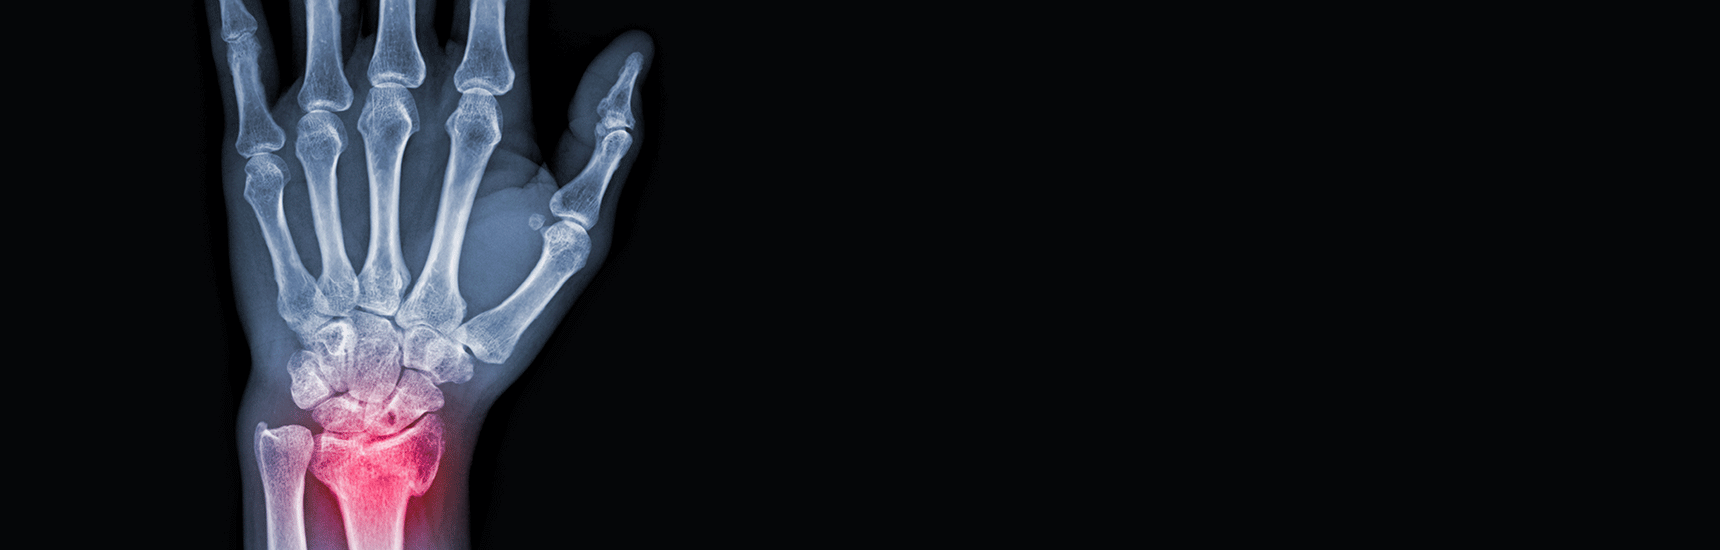

Möglichst gesund alt zu werden und ein langes und schmerzfreies Leben führen zu können, ist ein Wunsch der meisten Menschen. Eine wichtige Rolle, vor allem im Bereich der Schmerzvermeidung, spielt dabei der Bewegungsapparat. Viele Menschen verlieren im Alter zunehmend an Mobilität, Muskeln verlieren an Kraft und Masse, Knochen werden anfälliger für Brüche und Gelenke zeigen schmerzhafte degenerative und entzündliche Veränderungen. Die Med Uni Graz ist an der EU-geförderten COST-Initiative namens „GEMSTONE“ beteiligt, deren Mitglieder die klinischen und molekularbiologischen Aspekte solcher muskuloskelettaler Erkrankungen analysieren. Ziel ist es unter anderem, den Grundstein für zukünftige klinische Anwendungen und Behandlungen von Krankheiten zu legen.